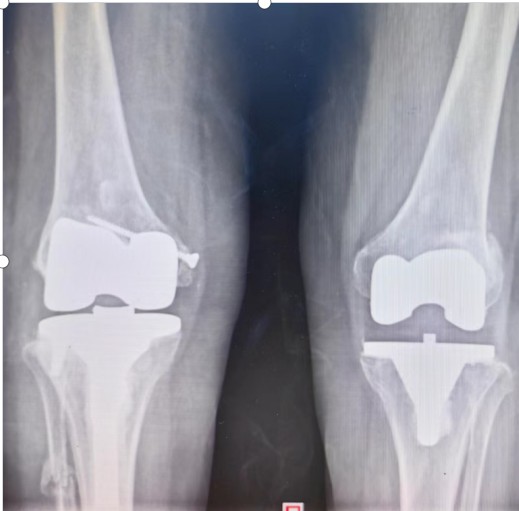

羅湘平主任醫(yī)師團(tuán)隊考慮患者的家庭經(jīng)濟狀況,決定力爭修復(fù)患者原有的解剖結(jié)構(gòu),避免使用更多的人工替代品,以減少患者的經(jīng)濟負(fù)擔(dān)。為了能夠順利完成手術(shù)、達(dá)到滿意的效果,羅湘平主任醫(yī)師做好充分的術(shù)前準(zhǔn)備工作,精心設(shè)計手術(shù)方案,選擇為患者實施普通的人工膝關(guān)節(jié)置換,內(nèi)側(cè)副韌帶止點采用螺絲重建術(shù)恢復(fù)膝關(guān)節(jié)穩(wěn)定性,脛骨外側(cè)平臺骨缺損采用螺絲釘加骨髓泥充填,為患者節(jié)省3萬余元材料費。劉奶奶的膝關(guān)節(jié)畸形得到矯正、恢復(fù)了穩(wěn)定性,于術(shù)后第10天順利出院。

術(shù)后

術(shù)后一年